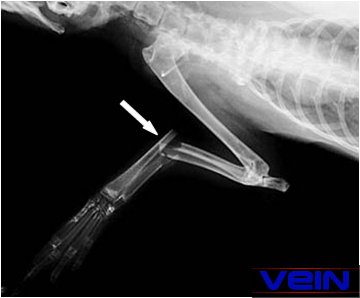

uspokoić królika. Prześwietlenie

oraz kompletne badanie fizyczne i neurologiczne musi być wykonane w celu

określenia uszkodzeń, dalszego leczenia i przewidywań

dotyczących gojenia się rany.

Użycie

zespolenia śródszpikowego Technika zespolenia

śródszpikowego przy pomocy gwoździa jest często stosowana u małych

zwierząt i stosunkowo prosta. Niezależnie od tego wymaga

Gwóźdź lub igła musi bezwzględnie zająć 60 do

70% jamy szpikowej.